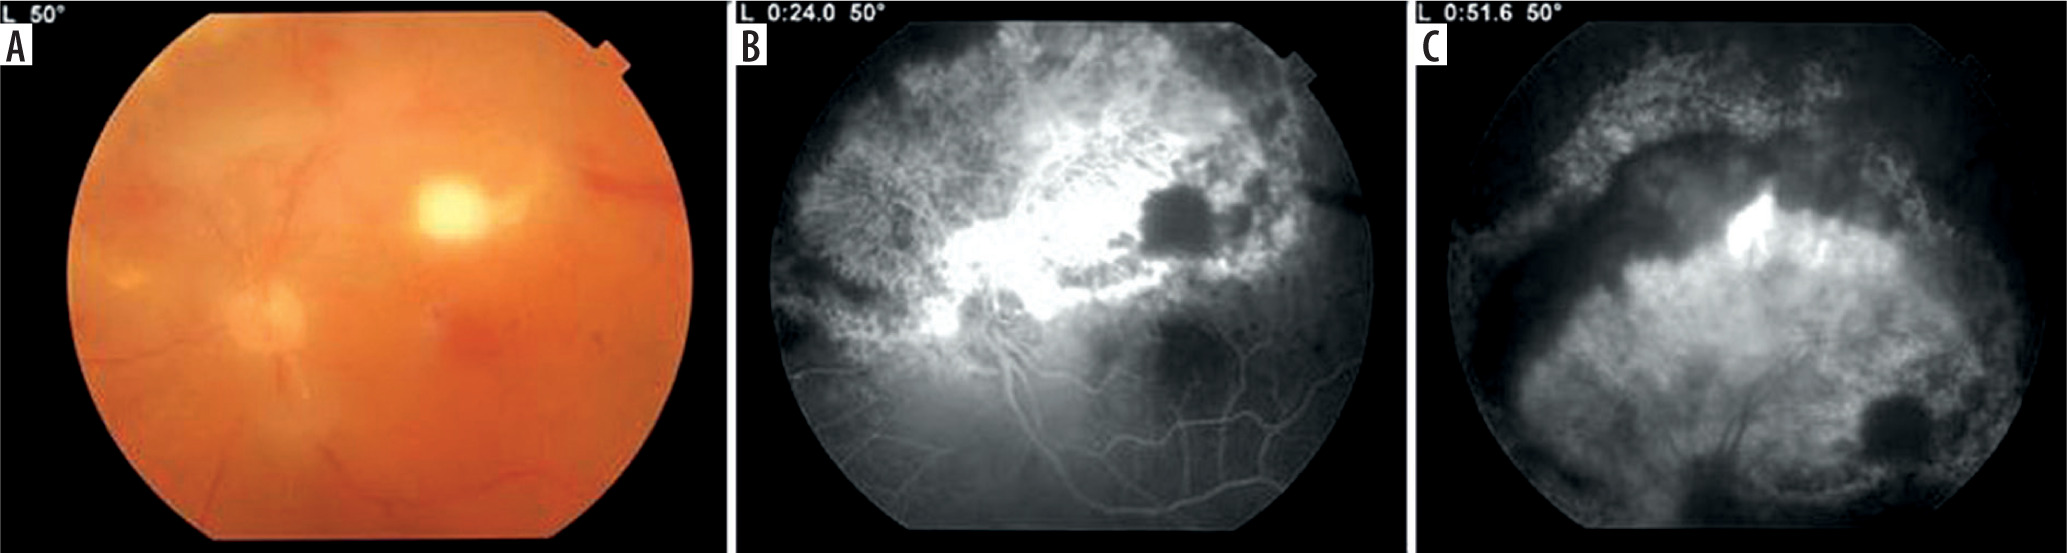

A 54-year-old woman was hospitalized due to necrotic retinitis of her left eye (LE). She noticed floaters and decrease of visual acuity (VA) one month earlier with concomitant general weakness. As she experienced the similar floaters in her right eye (RE) about one year earlier with its spontaneous resolution, she did not initially seek medical attention. Her medical history was notable for peripheral spondyloarthropathy (HLA-B27+) for 10 years. The disease had been controlled by oral MTX 25 mg once weekly for 3 years, methylprednisolone 3 mg daily for 10 years, and nonsteroidal anti-inflammatory drugs (NSAIDs). She also suffered from post-steroidal diabetes and osteoporosis. At admission her VA (Snellen) was 1.0 and 0.4 for RE and LE, respectively. Right eye showed atrophic perifoveal scar (Figure 1A) and LE mild anterior segment inflammation. Fundus eye examination found vitreous inflammatory opacities and large nonhomogeneous inflammatory lesion with signs of diffuse arteritis (Figure 1B). Fluorescein angiography (FA) showed the hypofluorescence area with hyperfluorescent center (Figure 1C). Serology testing was notable for toxoplasma (IgG > 200, positive if > 3.0, and IgM 0,48, negative if < 0.5), cytomegalovirus (CMV; IgG 177, positive if > 6.0, IgM not reactive) and herpes zoster virus (HZV; IgG 448.47, positive if > 110, IgM negative). Syphilis, HIV, and herpes virus type 1 and 2 were negative. Blood count revealed slightly decreased levels of monocytes and lymphocytes. Methotrexate treatment was discontinued due to immunosuppression. Oral trimethoprim/sulfamethoxazole (TS) twice a day and clindamycin 1 mg intravitreally twice with an interval of 5 days were given. Additionally, oral acyclovir 800 mg 5 times per day was prescribed. In the following 10 days of hospitalization, the inflammation decreased and VA increased to 0.5 (Figure 1D). Patient was discharged from the hospital on methylpredniso-lone and TS. At the 3-week follow-up, massive retinal neovascularization was found with persistent retinal inflammation (Figure 2A–C). Two complementary intravitreal injections of clindamycin resulted in rapid improvement. The signs of arteritis almost disappeared, and panretinal photocoagulation was urgently done. Prophylactic doses of TS (1 tablet every 3 days) were prescribed. On follow-up, VA was gradually decreasing to 0.02 due to progressive macular edema and membrane (Figure 3A). At the 8-month follow-up visit spontaneous posterior vitreous detachment (PVD) with concomitant vitreous hemorrhage occurred and VA was hand movements (Figure 3B). Anti-VEGFs (aflibercept twice and faricimab once) were injected in case of macular edema aggravation. At the 18-month follow-up visit VA was 0.1 (Figure 3C).

Figure 2

A) Fundus photography 3 weeks after discharge with macular infiltrate typical for toxoplasmosis with less pronounced arteritis. B) Fluorescence angiography of early phase with hypofluorescent macular focal lesion and massive hyperfluorescent retinal neovascularization. C) Leakage from the new vessels, hypofluorescent arcuate active lesion between atrophic retina and neovascularization and no perfusion of vessels in the superior hemisphere